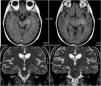

Los ganglioglioma son tumores bien diferenciados, de crecimiento lento, compuestos por una mezcla de células ganglionares maduras y gliales. La mayoría son de gradoI de la OMS. Aparecen predominantemente en niños y adultos jóvenes. La mayoría se localizan a nivel del lóbulo temporal, y la sintomatología más frecuente son las crisis epilépticas de difícil control farmacológico. En general tienen buen pronóstico tras la resección quirúrgica. La variante anaplásica, considerada gradoIII de la OMS, presenta mayor agresividad clínica y radiológica. La diseminación leptomeníngea es excepcional en estos tipos de tumores, pero cuando es diagnosticada presenta un curso rápidamente progresivo y fatal para el paciente.

Gangliogliomas are well-differentiated, slow-growing tumors. The majority are gradeI of WHO. It appears predominantly in children and young adults. Most are located at the temporal lobe, and as symptomatology more frequent epileptic seizures of difficult pharmacological control. In general, they have a good prognosis after surgical resection. The anaplasic variant, considered to be gradeIII of the WHO, presents greater clinical and radiological aggressiveness. Leptomeningeal dissemination is exceptional in these types of tumors, but when diagnosed it presents a rapidly progressive and fatal course for the patient.